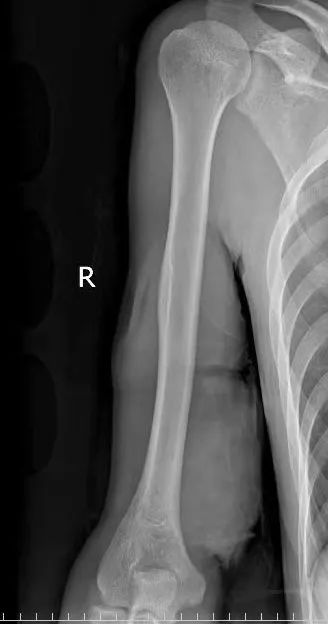

診斷為:

右上臂開放性傷口

右上臂肱動脈斷裂

右上臂正中神經牽拉傷

右上臂肌肉斷裂

右上臂尺神經、肌皮神經

前臂內側皮神經斷裂

發(fā)現(xiàn)小悅右上臂

傷口深及骨質

創(chuàng)面滲血且污染嚴重

多個肌腱及肌肉斷裂劃破動脈